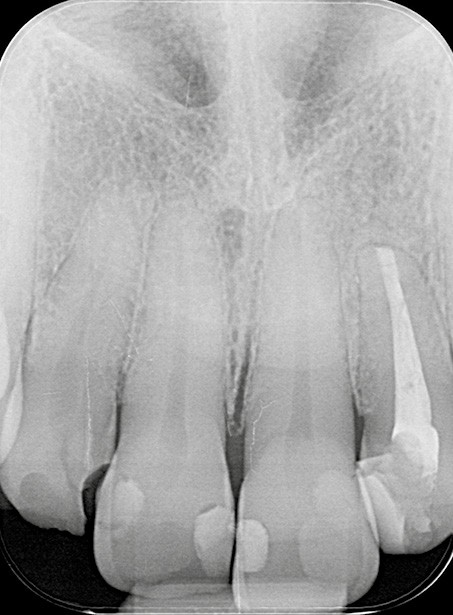

- un retraitement orthograde présente un mauvais rapport bénéfice-risque : par exemple, la présence d’un tenon dont la dépose pourrait fracturer la dent (fig. 2a-b) ;